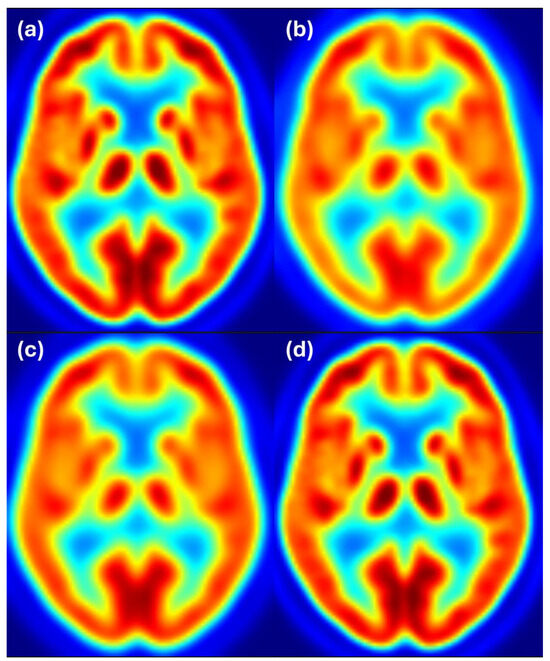

To complement the quantitative results, we provide visual examples of harmonization outcomes for two representative scanner combinations. Figure 4 shows axial slices for 8 mm target resolution for Discovery matching HR+ resolution. It shows that the Discovery image after filtering with the estimated filter is almost the same as the Discovery image filtered to 8 mm resolution. Both images also closely resemble the reference image from the HR+ scanner with 8 mm resolution.

Figure 4. Harmonization results for the Discovery scanner matching the HR+ images filtered to 8 mm resolution. Image (a) shows the unfiltered Discovery image, (b) shows the HR+ image at the target resolution of 8 mm, (c) shows the Discovery image after filtering with the estimated filter, and (d) shows the Discovery image filtered to 8 mm resolution. Color scale indicates FDG uptake levels: red for high, green/yellow for medium, and blue for low uptake.